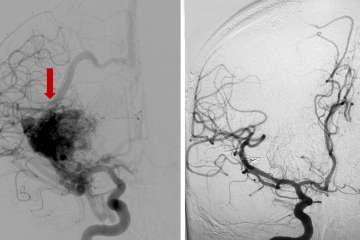

Anterior-Posterior view of a cerebral angiogram demonstrating severe right middle cerebral artery stenosis (red arrow) due to acute clot formation on a brain vessel atherosclerotic plaque before treatment (left) and after treatment (right).